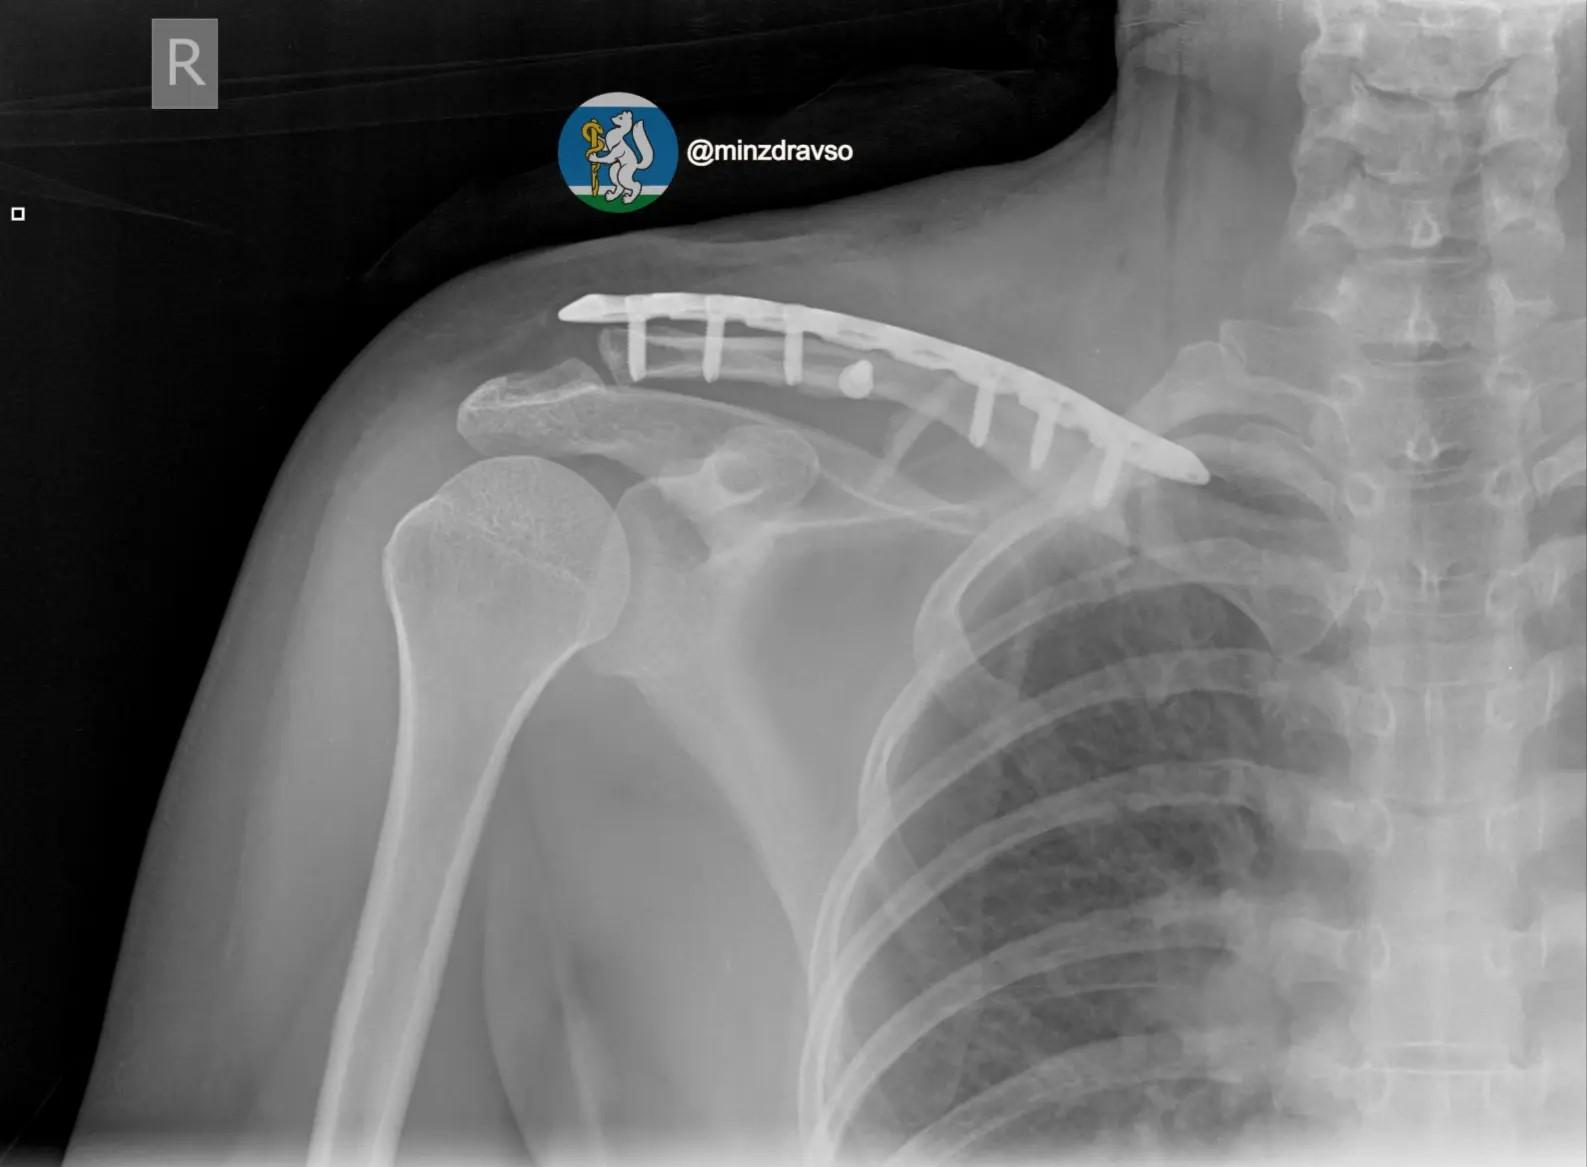

В январе в Екатеринбурге автомобиль сбил 44-летнюю женщину, а затем переехал её. Пострадавшую госпитализировали с тяжелыми повреждениями: черепно-мозговая травма, ушиб головного мозга, оскольчатый перелом правой ключицы и раздробленные кости таза.

В региональном минздраве пояснили: «Крайне тяжелое повреждение таза представляло высокий риск массивной кровопотери, поэтому борьба за жизнь пациентки началась с немедленной стабилизации ее состояния. Медики качественно скрепили отломки всех поврежденных сегментов костей и таза аппаратами внешней фиксации».